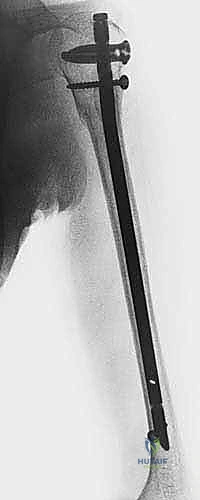

5. إدخال المسمار النخاعي (Nail Insertion):

يتم اختيار مسمار التيتانيوم بالطول والقطر المناسبين اللذين تم قياسهما مسبقاً، ويتم إدخاله بلطف فوق سلك التوجيه حتى يعبر منطقة الكسر ويستقر في مكانه المثالي.

6. القفل الديناميكي والاستاتيكي (Locking):

لمنع المسمار من الدوران أو الانزلاق، يجب تثبيته ببراغي عرضية. يتم إدخال البراغي العلوية في الكتف عبر جهاز توجيه متصل بالمسمار. أما البراغي السفلية (فوق الكوع)، فتتطلب مهارة فائقة؛ حيث يتم إدخالها عبر شقوق صغيرة جداً (1 سم) باستخدام تقنية "اليد الحرة" (Freehand Technique) تحت توجيه الأشعة، مع حماية العصب الكعبري والأوعية الدموية بدقة.